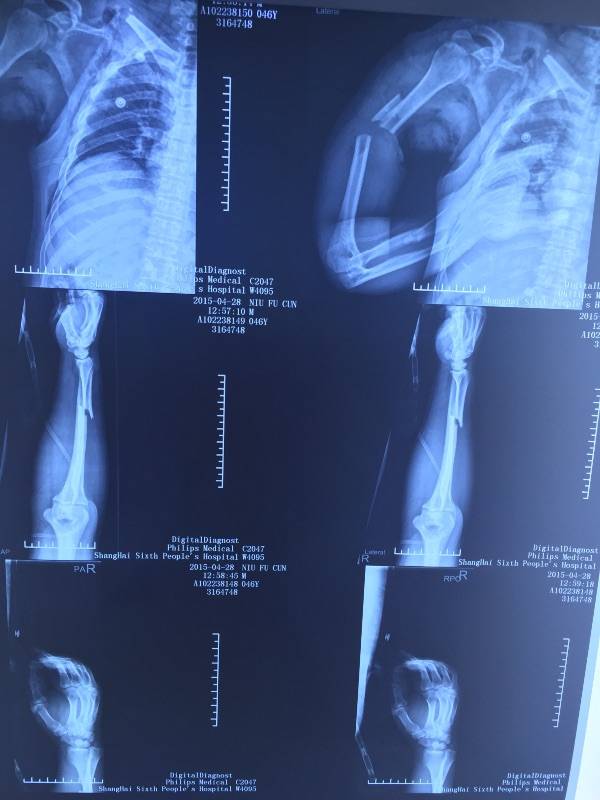

[断指再植] 肩胛带离断再植一例

肩胛带离断,再植风险很高,由于肢体肌肉多,出现肾功能损害几率增加。高手!

期待术后